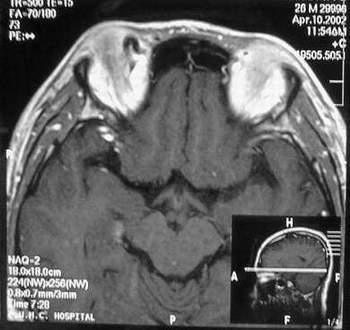

MRI及增强结果如下:

患者压颈及其它Valsava试验结果阴性。从MRI分析,在T1、T2、T+C检查该支血管均为明显流空现象,说明该血管血流速度很快,而从走行和分布看,眼上静脉可能性很大。也许也不能除外异常的眼动脉或异常血管。眶内主要可能的血管病变包括颈内动脉海绵窦瘘(高流窦)、AVM、眼眶静脉曲张、海绵状血管瘤、静脉性血管瘤、毛细血管瘤和眶内动脉瘤。。 1、颈内动脉海绵窦瘘:该患者临床有一部分支持该诊断。但从影像分析,海绵窦未见明显扩张;眼外肌未见明显充血扩张的长T1、长T2信号;颈内动脉海绵窦瘘常可见继发到血栓,可见到短T1、长T2的血栓信号。 2、眼眶静脉曲张:该疾患一般常见于小儿。该患大多数会出现Valsava试验阳性,间歇性突眼。不符合该患。影像学检查,于曲张静脉内常可见血栓和静脉石。所以不符合该患。 3、AVM:患者目前的影像学资料尚不全面,但可符合该诊断。临床上改病常见于30岁左右年轻人,单侧发病,于本患较符合。问题在于临床没有明确的血管杂音,似乎难以解释。 4、该患影像学与海绵状血管瘤差别很大,所以可基本排除此诊断。 5、静脉性血管瘤和毛细血管瘤:MRI中等T1、长T2信号,较易与本病鉴别。 6、眶内动脉瘤:我觉得患者并不能排除本病,但同样,由于波动性阴性,似乎也难以解释。 纵上所述:本人觉得,患者AVM可能性较大,同时不能除外眶内动脉瘤。 关于进一步检查,我觉得DSA价格过于昂贵。是否可先进行彩色多普勒检查,首先可以明确是静脉系统还是动静脉瘘抑或是动脉瘤。第二步,可进行MRA检查,可以清楚地显示海绵窦地相关关系,并可借此诊断或排除颈内动脉海绵窦瘘。如还需第三部检查,可进行MRV检查,对静脉系统进一步评价。三种检查总共的费用2000多圆,但给予我们的信息量已经很丰富了。 敬请各位医师提出自己的见解。 谢谢!

根据MRI显示眼上静脉扩张可能性很大。眼上静脉扩张有几种原因:1.颈内动脉海绵窦瘘,2.眶尖肿瘤,3.甲亢,4.炎性假瘤.病人球结膜充血示静脉回流障碍,动脉瘤可能性小.根据病史,我认为排除1,2.则考虑3,4.查T3,T4.激素作诊断性治疗.